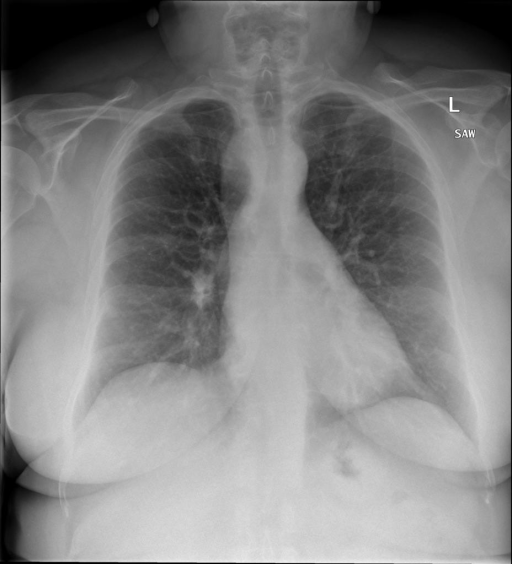

- (1)准备[诊疗报告(中文)](./data/Xray/openi-zh.json)和[X光影像](https://pan.baidu.com/s/13GBsDMKf6xBZBSHpoWH_EA?pwd=k9sh)在`data/Xray`文件夹下; - (2)开始训练: ```bash # 设置CUDA变量,主要是为了解决有时候直接训练而出现无法正确加载到显卡问题 export CUDA_VISIBLE_DEVICES=0,1,2,3 # 开始训练 bash finetune_XrayGLM.sh ``` 这里的复现过程非常简单,主要是很多过程我们都为大家准备好了,大家可以随时复现一个自己的`XrayGLM`。 ### 4.模型训练(通用) - [【官方视频教程】XrayGLM微调实践](https://www.bilibili.com/video/BV1Yh4y147gx/) - [复旦大学《大语言模型理论与实践》](https://intro-llm.github.io/) ## 效果展示 *以下效果来自于**低质量**的数据训练和权重 影像诊断: |X光影像|诊疗报告(医生)|XrayGLM| |:-|:-|:-| |![](./data/Xray/2_1.png)|根据X射线图像,心脏大小正常,肺部看起来很清晰。已经排除了肺炎、积液、水肿、气胸、腺病、结节或肿块的存在。该发现表明一切正常。换句话说,总体印象是胸部正常。|X光片显示,心脏大小正常。肺部没有气胸或胸腔积液的证据。骨骼结构看起来没有任何异常。总的来说,X光片表明没有发现急性心肺疾病的迹象。| |![](./data/Xray/2882_1.png)|X光图片显示没有扭曲的区域、可疑的骨质不透明度或胸腺积液。心脏大小轻微增大,但非常稳定。此外,没有气胸的证据,肺野也正常。总体来说,X光片显示没有急性心脏异常,但要注意轻微的心脏扩大。|X光片显示,心脏大小正常。肺部和纵隔轮廓清晰,没有气胸或胸腔积液的证据。骨骼结构完整,没有任何急性异常。| |![](./data/Xray/2577_1.png)|心影形态在正常范围内。没有急性骨质异常。有可能出现没有明显的吸水或肺实质状况的线索。没有大面积积液或气胸。有可能怀疑其有误吸或肺实质问题。为了确诊和治疗,可能需要进行适当的影像学随访。|心脏大小正常,肺部和纵隔轮廓清晰。没有急性异常或活动受限的证据。没有任何明显的气胸、胸腔积液或肺不张的迹象。此外,也没有发现任何局灶性骨质异常或其他急性疾病。| 多轮对话: |X光影像|诊疗报告(医生)| |:-|:-| |![](./data/Xray/861_1.png)|右侧主动脉突出观察到。心脏大小正常。胸部未发现明显的肺气肿、胸膜积液或可疑的肺部病变。报告指出已知右侧主动脉情况正常。| ```bash >> X光影像路径:./data/Xray/861_1.png >> 用户:这是一张什么图? >> XrayGLM:这张图片显示的是一张肺部检查的X光片。 >> 用户:请描述这张胸部X光片的诊断结果 >> XrayGLM:心脏大小正常,肺部清晰。没有急性心肺疾病的证据。 >> 用户:是否存在肺气肿? >> XrayGLM:没有肺气肿。心脏大小正常,肺部清晰。没有发现急性心肺疾病的证据。 >> 用户:平时饮食该注意什么? >> XrayGLM:饮食应该健康,均衡。建议增加蛋白质的摄入量,因为蛋白质有助于维持肌肉和骨骼的健康。多食用蔬菜、水果、全谷物以及健康的脂肪来源如橄榄油、鱼类等可以帮助获得足够的维生素和矿物质。此外,避免过度饮酒或吸烟,这些习惯可能会对心脏健康产生负面影响。 ``` ## 未来展望 1. 模型的能力更多来源于数据的支持,`OpenI-zh`作为微调数据集,其数据量足以支持研究,在更广泛的任务和性能表现上,我们认为**在大规模数据集上预训练并在高质量少量数据集上微调是一种可行的方案**; 2. 普遍意义的理解上,视觉多模态模型=视觉模型+语言模型。除了需要关注视觉模型信息与语言模型输出的搭配外,还需要**额外关注到语言模型的加强,在人机的对话中,尤其是医疗语言模型的问答上,除了专业的医疗问题回答,带有人文情怀的有温度的回答更应该是我们追寻的目标**。 3. **高精度的模型永远打不过大参数的模型**,如果在6B模型和13B模型上选择微调,请在资源充足情况下选择13B的大参数模型; ## 项目致谢 1. [VisualGLM-6B](https://github.com/THUDM/VisualGLM-6B)为我们提供了基础的代码参考和实现; 2. [MiniGPT-4](https://github.com/Vision-CAIR/MiniGPT-4)为我们这个项目提供了研发思路; 3. ChatGPT生成了高质量的中文版X光检查报告以支持XrayGLM训练; 4. [gpt_academic](https://github.com/binary-husky/gpt_academic)为文档翻译提供了多线程加速; 5. [MedCLIP](https://github.com/RyanWangZf/MedCLIP) 、[BLIP2](https://huggingface.co/docs/transformers/main/model_doc/blip-2) 、[XrayGPT](https://github.com/mbzuai-oryx/XrayGPT) 等工作也有重大的参考意义; ![](./assets/images/mpu.png) 这项工作由[澳门理工大学应用科学学院](https://www.mpu.edu.mo/esca/zh/index.php)硕士生[王荣胜](https://github.com/WangRongsheng) 、[段耀菲](https://github.com/IsBaSO4) 、[李俊蓉](https://github.com/lijunrong0815)完成,指导老师为檀韬副教授、[彭祥佑](http://www.patrickpang.net/)老师。 *特别鸣谢:[USTC-PhD Yongle Luo](https://github.com/kaixindelele) 提供了有3000美金的OpenAI账号,帮助我们完成大量的X光报告翻译工作 ## 免责声明 本项目相关资源仅供学术研究之用,严禁用于商业用途。使用涉及第三方代码的部分时,请严格遵循相应的开源协议。模型生成的内容受模型计算、随机性和量化精度损失等因素影响,本项目无法对其准确性作出保证。即使本项目模型输出符合医学事实,也不能被用作实际医学诊断的依据。对于模型输出的任何内容,本项目不承担任何法律责任,亦不对因使用相关资源和输出结果而可能产生的任何损失承担责任。 ## 项目引用 如果你使用了本项目的模型,数据或者代码,请声明引用: ```bash @misc{wang2023XrayGLM, title={XrayGLM: The first Chinese Medical Multimodal Model that Chest Radiographs Summarization}, author={Rongsheng Wang, Yaofei Duan, Junrong Li, Patrick Pang and Tao Tan}, year={2023}, publisher = {GitHub}, journal = {GitHub repository}, howpublished = {\url{https://github.com/WangRongsheng/XrayGLM}}, } ``` ## 使用许可 此存储库遵循[CC BY-NC-SA](https://creativecommons.org/licenses/by-nc-sa/4.0/) ,请参阅许可条款。